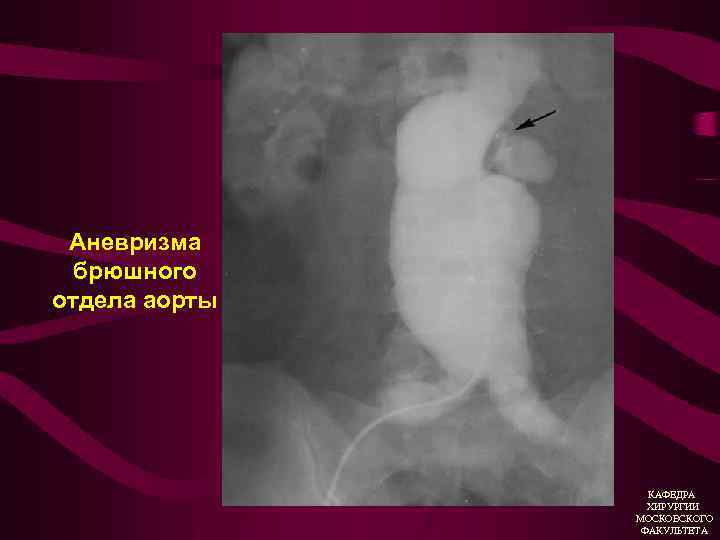

Аневризма брюшного отдела аорты КАФЕДРА ХИРУРГИИ МОСКОВСКОГО ФАКУЛЬТЕТА

Атеросклеротическая аневризма брюшной аорты • Боль (симптомная аневризма) • Атеросклеротический анамнез • Пульсирующее образование в брюшной полости, аускультативно систолический шум • УЗИ (дуплексное ангиосканирование) • Ангиография КАФЕДРА ХИРУРГИИ МОСКОВСКОГО ФАКУЛЬТЕТА

Дилятирующий атеросклероз Аневризмы 1. Истинная (расширение аорты или артерий в 2 раза и более без дефекта стенки 2. Ложная (паравазальная организованная пульсирующая гематома, вследствие дефекта в стенке аорты или артерии). КАФЕДРА ХИРУРГИИ МОСКОВСКОГО ФАКУЛЬТЕТА